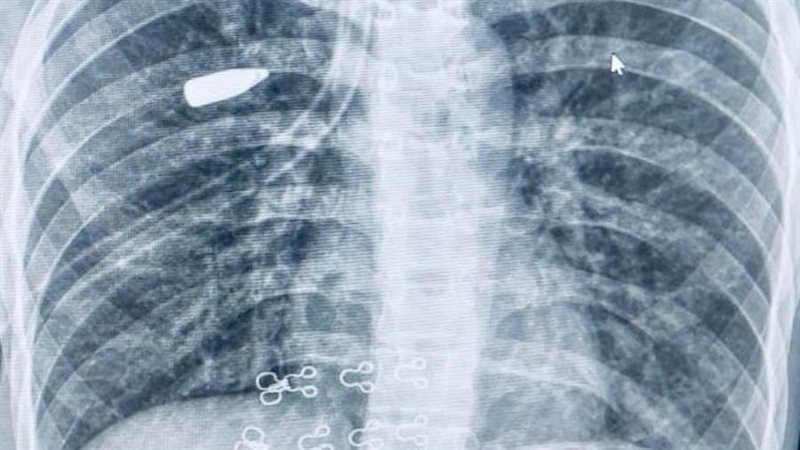

وعلى الفور، قام الفريق الطبي بإجراء الفحوصات والإجراءات اللازمة، والتي كشفت عن استقرار المقذوف الناري داخل أنسجة الرئة اليمنى ليتم التنسيق مع مستشفى القلب الجامعي، ويتم تشكيل فريق طبي تحت إشراف الأستاذ الدكتور محمد عياد، وبرئاسة الدكتور محمد فاروق عبد الحافظ، مدرس جراحة القلب والصدر، وضم كلا من، الطبيب علي زين، مدرس مساعد بالقسم، والطبيب محمد ببلاوي، والطبيب مروان أحمد، أطباء مقيمين بالقسم، يعاونه فريق طبي من قسم التخدير والرعاية المركزة تحت إشراف الأستاذة الدكتورة هالة سعد رئيس القسم، وضم كلا من الدكتور عبد الرحمن حمدي، مدرس التخدير والرعاية المركزة، والطبيب أحمد وهبه مدرس مساعد بالقسم، بينما ضم الطاقم التمريض الجراحي المتميز كل من، أخصائي تمريض كيرلس جمال، وفني تمريض خالد مصطفى، وفني تمريض هند عبد المنعم.

وتمت مناظرة دقيقة للحالة وإجراء الأشعات اللازمة التي أكدت استقرار المقذوف بين أغشية الرئة، ليقوم الفريق الطبي بإجراء جراحة دقيقة للغاية، وتم استخراج المقذوف الناري بنجاح باستخدام منظار الصدر الجراحي من خلال فتحة جراحية لا تتعدى 2 سم، مما ساهم في الحفاظ على سلامة الرئة وتقليل التلف إلى أدنى حد، بالإضافة إلى الحفاظ على الشكل الجمالي لجدار الصدر.